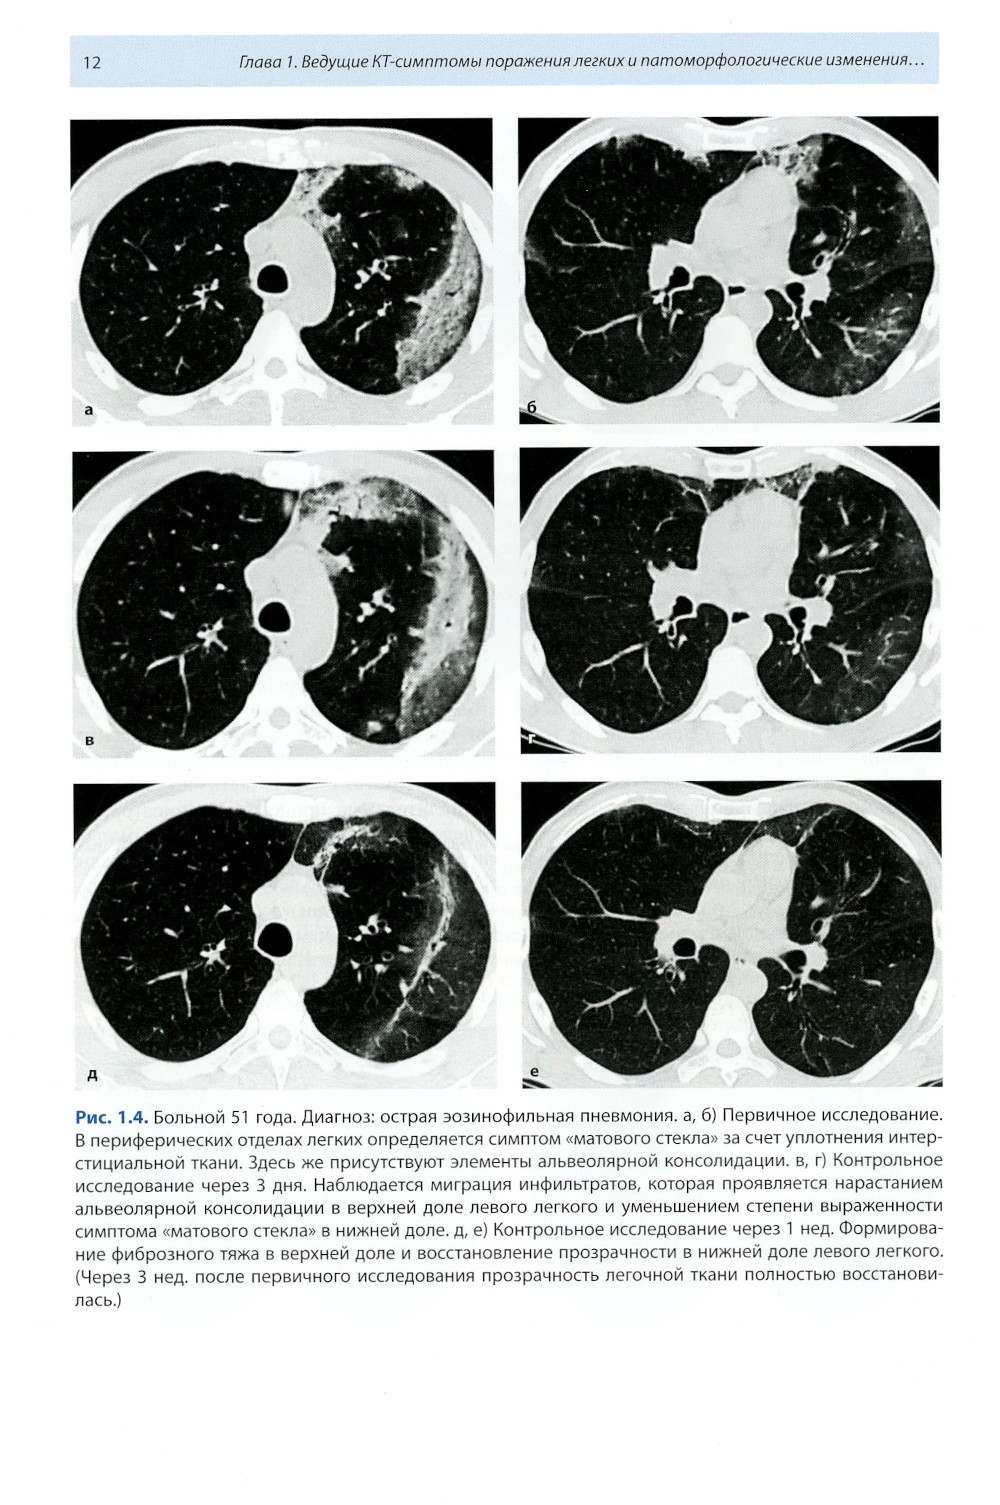

Книга составлена из двух разделов. В первом (глава 1) описаны основные симптомы патологии легких, выявляемые при КТ. Каждый из них представлен с позиции отображающих его морфологических изменений. В краткой форме описаны заболевания, проявляющиеся конкретным симптомом. Второй раздел книги состоит из трех глав, в которых отражены современные взгляды на наиболее часто встречающуюся патологию легких (пневмония, туберкулез, рак) и показаны возможности КТ в выявлении этих заболеваний. Издание предназначено для врачей лучевой диагностики, терапевтов, интернов и студентов старших курсов, интересующихся проблемами рентгенологии.| Издательство | МЕДпресс-информ |